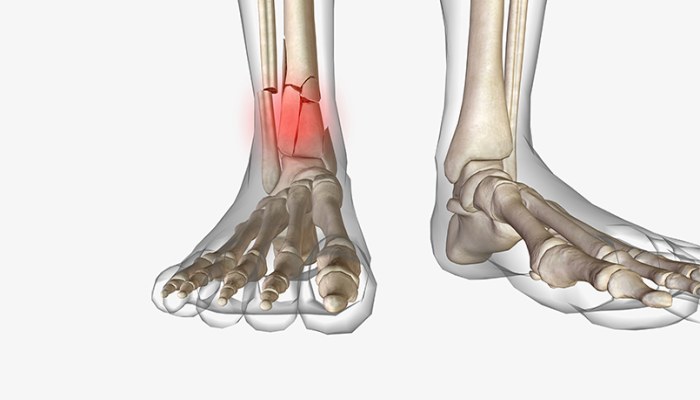

- شکستگی مالئول خارجی: این نوع رایجترین نوع شکستگی مچ پا است. مالئول، برآمدگی بیرونی مچ پا است که در انتهای نازکنی (فیبولا) قرار دارد و زمانی رخ میدهد که مچ پا پیچ بخورد یا به پهلو خم شود.

- شکستگی مالئول داخلی: مالئول داخلی به برآمدگی داخلی مچ پا گفته میشود که در انتهای درشتنی (تیبیا) قرار دارد.

- شکستگی دوقوزکی یا Bimalleolar ankle fracture: زمانی که قوزک داخلی و خارجی پا دچار شکستگی شود به آن شکستگی دوقوزکی گفته میشود که دومین شکستگی رایج مچ پا است. معمولاً برای ترمیم این نوع آسیب، جراحی نیاز است.

- شکستگی سهقوزکی: به شکستگی همزمان مالئول داخلی، خارجی و خلفی اشاره دارد و عموماً برای ترمیم نیاز به جراحی است.